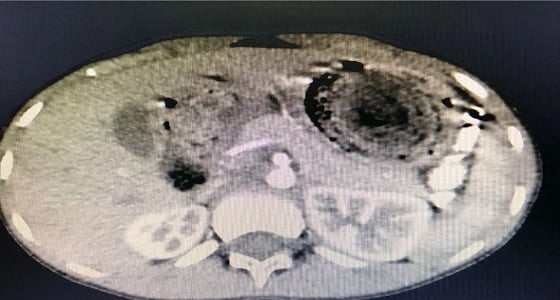

إجراء أول جراحة منظار بالقصيم لاسئصال كتلة محسوسة بمعدة طفل